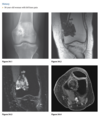

61yr old woman with shoulder pain

AP Radiograph of left shoulder in external and internal rotation (1 & 2) - globular foci of calcification in expected location of supraspinatus (White arrow) and infraspinatus (black arrow) and pectorals major

DIAGNOSIS: Hydroxyapatite deposition disease

(HADD)

HADD consists of crystal deposition in

and around joints, without a known cause.

AKA calcific tendonitis

On radiographs, the calcium deposits appear cloud-

like and amorphous and can involve the tendon,

ligament, bursa, or joint capsule. Intraarticular crys-

tal deposition can destroy the joint space, resulting

in a condition referred to as “Milwaukee shoulder.”

On CT,

­ accompanying erosion of the underlying bone can be

seen. CT appearance has been described as commonly

having a flame-shaped or comet-tail configuration of

the calcifications

If not in shoulder/region not common for HADD ?Malignancy